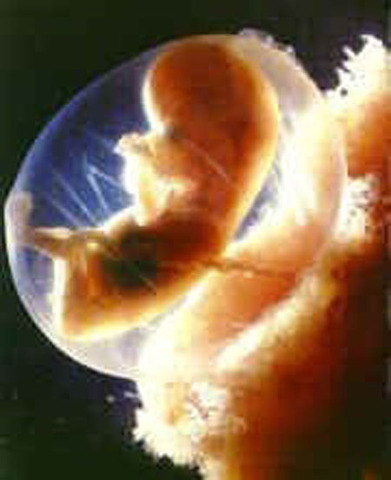

Hacia el final de esta semana, el cuerpo así como sus órganos estarán formados. Dejará de ser un embrión para convertirse en feto. En esta semana, crecen los dedos de las manos y pies. La cabeza es desproporcionalmente grande y constituye la mitad del embrión. Su crecimiento en el útero se ve facilitado por tener un cuerpo muy flexible, no tiene huesos, sino cartílagos.

Inicia el periodo fetal, que termina hasta el nacimiento. Comienzan a diferenciarse los caracteres sexuales primarios, determinados por la combinación de cromosomas, heredada en el momento de la fecundación. Los huesos empiezan a formarse, así como la lengua. Los ojos aún están cerrados. Los intestinos se encuentran en el cordón umbilical.